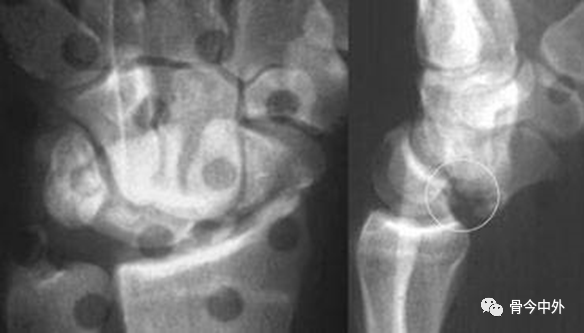

图1 成人期腕关节正侧位及舟骨蝶位片。1.舟骨;2.月骨;3.三角骨;4.豆状骨;5.大多角骨;6.小多角骨;7.头状骨;8.钩骨;9.桡骨茎突;10.尺骨茎突;11.第一掌骨基部。

图2 成人期腕关节正侧位及舟骨蝶位片。1.舟骨;2.月骨;3.三角骨;4.豆状骨;5.大多角骨;6.小多角骨;7.头状骨;8.钩骨;9.桡骨茎突;10.尺骨茎突;11.第一掌骨基部。

图3 成人期腕关节正侧位及舟骨蝶位片。12.舟骨结节。黑色箭头:舟骨腰部;白色箭头:舟骨滋养血管影。